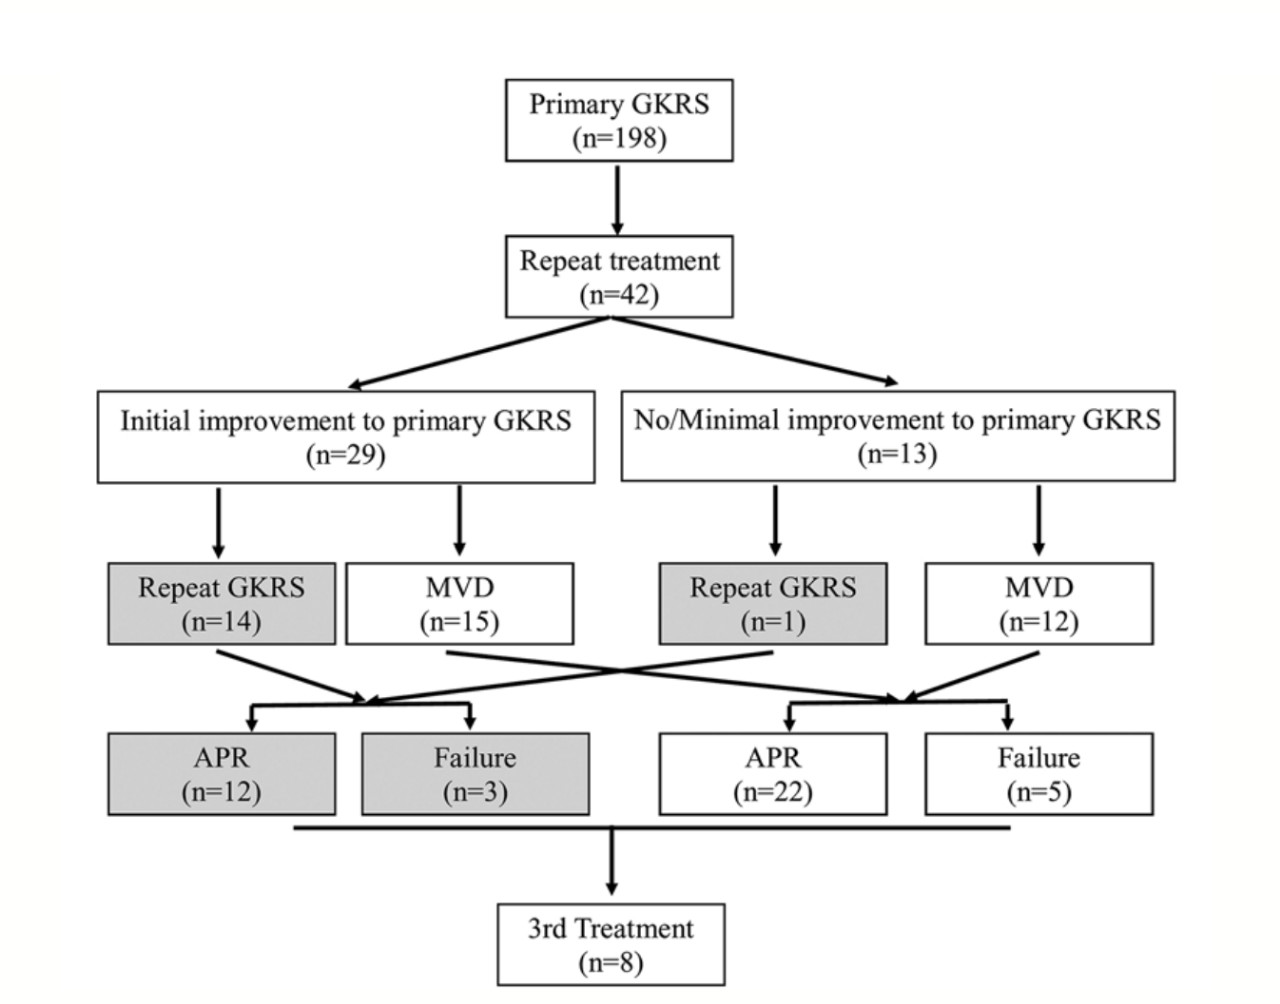

25. GKRS治疗三叉神经痛失败后重复伽玛刀放射外科手术与微血管减压术比较:系统评价和荟萃分析

Repeat Gamma Knife radiosurgery versus microvascular decompression following failure of GKRS in trigeminal neuralgia: a systematic review and meta-analysis

Author: Devi Prasad Patra, Amey Rajan Savardekar, Rimal Hanif Dossani, Vinayak Narayan, Nasser Mohammed and Anil Nanda

DOI: https://doi.org/10.3171/2018.5.JNS18583

伽玛刀放射外科(GKRS)已成为治疗经典三叉神经痛(TN)的一种有效方法。但是,几乎一半的患者GKRS后无效或病灶复发,通常需要再次治疗。现有文献没有证据表明,重复GKRS与微血管减压术(MVD)哪种方法更好。作者通过对文献进行系统回顾和荟萃分析以及对来本单位数据进行回顾性分析,试图比较GKRS失败后的TN接受GKRS或MVD的患者的总体预后。作者对PubMed,Cochrane图书馆,Web of Science和CINAHL数据库进行了系统的回顾和荟萃分析,分析最初GKRS治疗TN失败后,重复GKRS或MVD患者的资料。主要结局为1年时完全缓解疼痛(CPR)和部分缓解疼痛(APR)。次要结果是术后面部麻木率和再治疗率。合并的数据用R软件分析。使用漏斗图和I2检验分别评估偏差和异质性。共有22项研究符合入选标准,被纳入最终数据检索和荟萃分析。该研究未发现任何直接比较接受重复GKRS患者与经历MVD患者之间结局的对比研究。因此,作者的最终分析包括两组:描述重复GKRS后结果的研究(n=17)和描述MVD后结果的研究(n=5)。作者的机构研究是唯一可以直接比较两个队列的研究。对主要结局的汇总评估为:重复GKRS的患者83%和MVD的患者88%(p=0.49),重复GKRS的患者46%的患者CPR和MVD的患者72% (p=0.02)。次要结果的汇总估计是接受重复GKRS的患者中32%的面部麻木,接受MVD的患者中22%的面部麻木(p=0.11);接受重复GKRS的患者的再治疗率为19%,接受MVD的患者为13%(p=0.74)。作者的机构研究包括42例患者(15例重复GKRS,27例重复MVD),再治疗后1年的结果是80%重复GKRS的患者APR和81%MVD的患者(p=1.0) ;接受重复GKRS的患者中有47%达到了CPR,接受MVD的患者中有44%达到了CPR(p=1.0)。术后面部麻木或再治疗的发生率没有差异。作者认为,当前的荟萃分析未能在APR,术后面部麻木和再治疗率方面确定一种治疗方法优于其他治疗方法的任何优势。但是,与重复GKRS相比,MVD显示提供了更好的CPR机会。

图:美国路易斯安那州立大学史里夫波特医疗中心的三叉神经痛治疗方案。